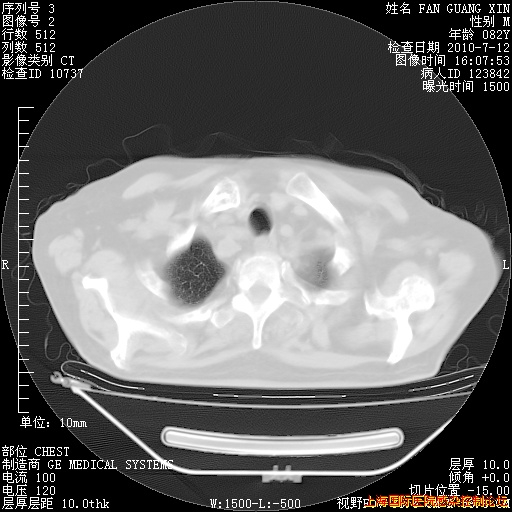

6月12日纵膈窗

整整相隔30天的肺部CT好像有所好转啊。甲强龙减量第3天,需要观察体温。

海管,自昨日你和我通完话后,不知您岳父消化道症状有无缓解?体温怎样?阅读7.12日胸部ct,个人认为目前激素治疗是有效的,甲强龙减量是适宜的。因在抗痨治疗,需密切观察肝功、肾功能和血常规。不过,老年、长期住院和大量使用激素,很担心菌群失调发生